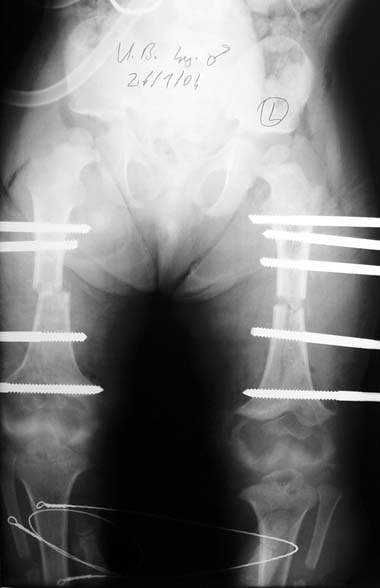

12-14 yaşları arasında Her iki tibiada toplam 10-15cm boy uzatma (iki seviyeli uzatma) Proksimal tibianın varus deformitesini proksimal osteotomi ile düzeltilmesi Distal tibianın varus deformitesi distal osteotomi ile düzeltmesi Distal tibianın varus deformitesi distal osteotomi ile düzeltmesi Boy uzatmanın sonunda lateral kollateral ligamentin gerilmesi Ortalama eksternal fiksasyon tedavi süresi = 8-10 ay